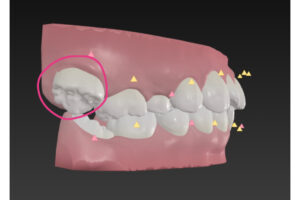

右上の だいに だいきゅうし は

下の歯の外側に出ていて

名前は はざみ状こうごう

英語ではシザーズバイト

この歯並びは下の歯と咬んでないので

食べ物を すりつぶすのが無理

シザーズバイト

㊙️のゴム掛けテクニックで矯正可能なので

安心して下さい